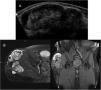

El hematoma crónico expansivo (HCE) es una lesión poco frecuente, caracterizada por la persistencia y aumento de tamaño del hematoma durante un periodo mayor de un mes desde la hemorragia inicial. La importancia clínica de esta patología se debe a que puede simular neoplasias malignas de partes blandas, tanto clínicamente por su crecimiento progresivo como por los hallazgos radiológicos. Este artículo revisará 3 casos de HCE en diferentes escenarios, explicando los hallazgos radiológicos en diferentes técnicas de imagen como ecografía, tomografía computarizada (TC), resonancia magnética (RM) y PET-TC.

Chronic expansive hematoma (CEH) is a rare lesion, characterized by the persistence and increase in size of an hematoma for a period greater than one month since the initial hemorrhage. The clinical importance of this pathology is due to the fact that it can simulate malignant soft tissue neoplasms, both clinically as a result of its progressive growth and radiologically for its findings in imaging studies. This article will review 3 cases of CEH in different scenarios, explaining the radiological findings in different imaging techniques such as ultrasound, computed tomography (CT), magnetic resonance imaging (MRI), and PET-CT.